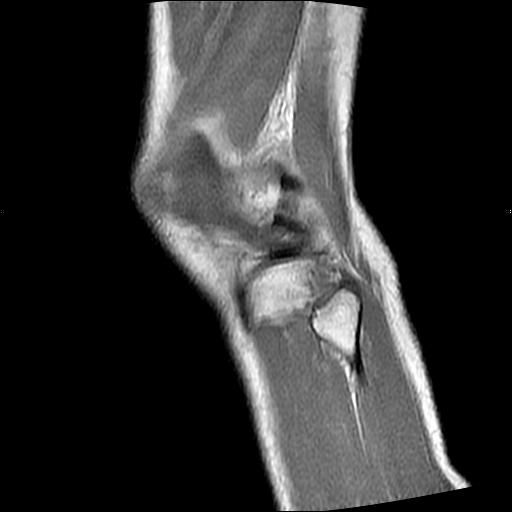

40岁男性,右膝关节外伤,x光平片示,髁间隆突撕脱骨折。

还有:

髁间隆突撕脱骨折;内侧副韧带损伤。

1、内侧副韧带撕裂;

2、前交叉韧带撕裂;

3、滑膜炎伴关节腔积液。

内侧副韧带撕裂及关节腔积液是肯定的,但是前交叉撕裂确定吗?会不会有容积效应的因素,因为前一张前交叉显示清楚,连续性良好,且较光滑。请问楼主有关节镜支持吗?我们医院也经常有这样的患者,但苦于没有关节镜,而无法对照、证实(除非完全断裂),出现了不同的诊断结果只能毫无意义的争论。

1、前交叉韧、内侧副韧带撕裂;

2、外侧半月板后角撕裂;

3、关节腔积液。4、髁间脊撕脱骨折。

除了关节积液外并无韧带撕裂,acl胫侧附着点有2束,正常情况下脂肪信号。此病例应加做压脂像以便观察是否有骨损伤。